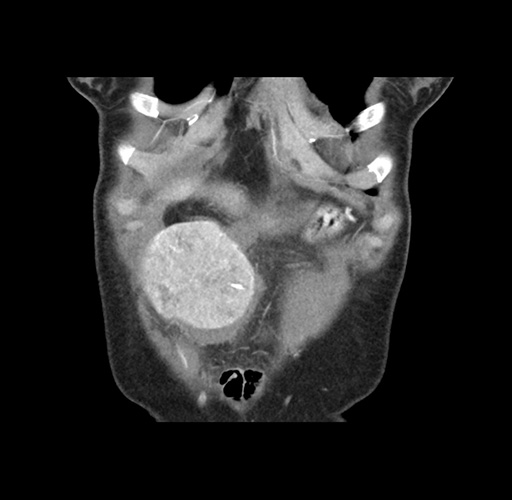

Imaging Analysis

Look through the patient's CT scan to identify any areas of concern for the necessary procedure.

Based on your CT findings, which issue(s) would give reason for "planned slowing down moment(s)" in this case?

Considering a standard left lateral sectionectomy procedure, what step(s) of the operation would you do differently in this case ?